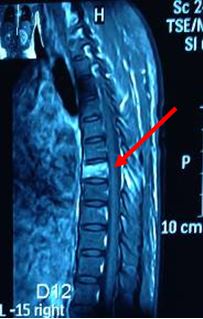

- Chụp cộng hưởng từ cột sống: Xẹp thân đốt sống D7, tổn thương thân đốt sông D2 và D9

Hình 7: Hình ảnh cộng hưởng từ cột sống sau điều trị 3 chu kỳ hóa chất: Tổn thương xẹp thân đốt sống D7, tổn thương thân đốt sống D2,D9